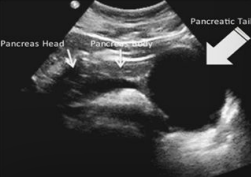

Describe this image

Differential dx?

A well-defined, solid, round, hypoechoic mass located in the head of the pancreas. Most likely adenocarcinoma but needs to be confirmed with biopsy